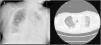

Our case represents a phenomenon equivalent to pseudo auto-PEEP, which is rationally explained by stress relaxation due to extreme inequalities in time constants. The flow-volume loop suggested an obstructive mechanism due to its biphasic morphology2,6 (Fig. 1C). However, this can be explained by the presence of two different lung-emptying compartments. These findings were confirmed by monitoring with EIT (video in Electronic Supplementary Material, ESM). Notice in Fig. 1A shows how the end-expiratory flow reached a level near 0. As shown in the radiological images (Fig. 2), there was a predominantly unilateral pathology with notable involvement of the left native lung. Finally, Fig. 1B shows how stress relaxation has an equivalent logarithmic fitting of both the inspiratory and expiratory phases, manifested in the progressive increase in end-expiratory pressure during the prolonged hold, which simulates the pseudo auto-PEEP phenomenon. In addition, this finding can be used as a parameter to evaluate the severity of lung injury.9